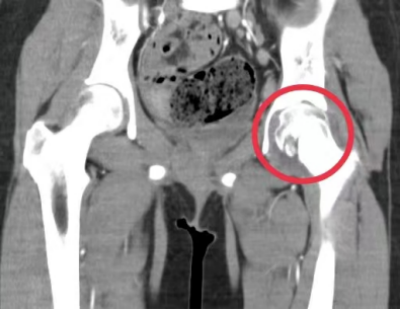

“入院时,患者左髋关节压痛明显伴活动障碍,立即为她完善了相关检查,关节MRI提示感染性病变,髋关节CT提示多发虫蚀样骨质破坏,肺部CT提示肺部多发结节样病变并钙化形成,不排除结核,结核菌素皮肤试验强阳性,γ-干扰素释放试验(T-SPOT)阳性,结合病史,进一步安排了关节穿刺并组织活检,病理证实为髋关节结核。”据儿科副主任、副主任医师周海依介绍,明确为左侧髋关节结核、原发性肺结核后,医护团队为孩子制定了抗结核治疗计划,经过精心的治疗和细致的护理,琪琪的病情好转,疼痛的症状逐渐得到控制,目前仍在住院接受治疗。

(左髋关节CT提示左股骨头多骨质破坏)